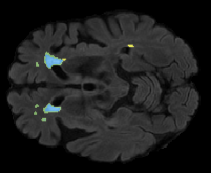

We evaluated our method in segmenting WMH from T1-w images using: a) Synthesized FLAIR images by treating the synthesis as a preprocessing step – we will refer to this method as offline synthesis; b) Synthesized FLAIR images using the proposed method, and c) without any synthesis – we will refer to this method as Unimodal. Baseline methods are illustrated in Figure 2

Table 2: Segmentation results for all proposed methods, each column represent a different slide in the image, blue areas are regions which were correctly labeled, false positives are shown in green, and false negatives in yellow

In order to better understand the above results, we visually analyzed the output segmentation performed for each method. Table 2 shows the results for three different slices (one slice per column). As illustrated, the proposed method is able to produce less false positives. It is also important to note that, unimodal segmentation is the one that produces more false positives, showing the advantage of using synthetic data. Regarding the nature of false positives, it can be easy to see in the third column a large number of false positives are on the border of periventricular lesions for the Unimodal method in comparison to the proposed method. Also from the first and second column, it can be observed that Unimodal tend to produce more small regions of false positives near to cortical areas. Removing such false positives requires additional post-processing steps, therefore, it is of value avoid this kind of over-segmentation. It can also be noted that synthesis methods tend to produce the same kind of false negatives, this may be due to the blurring effects in synthesized images since the information available during testing is limited – which otherwise is available from a FLAIR sequence.